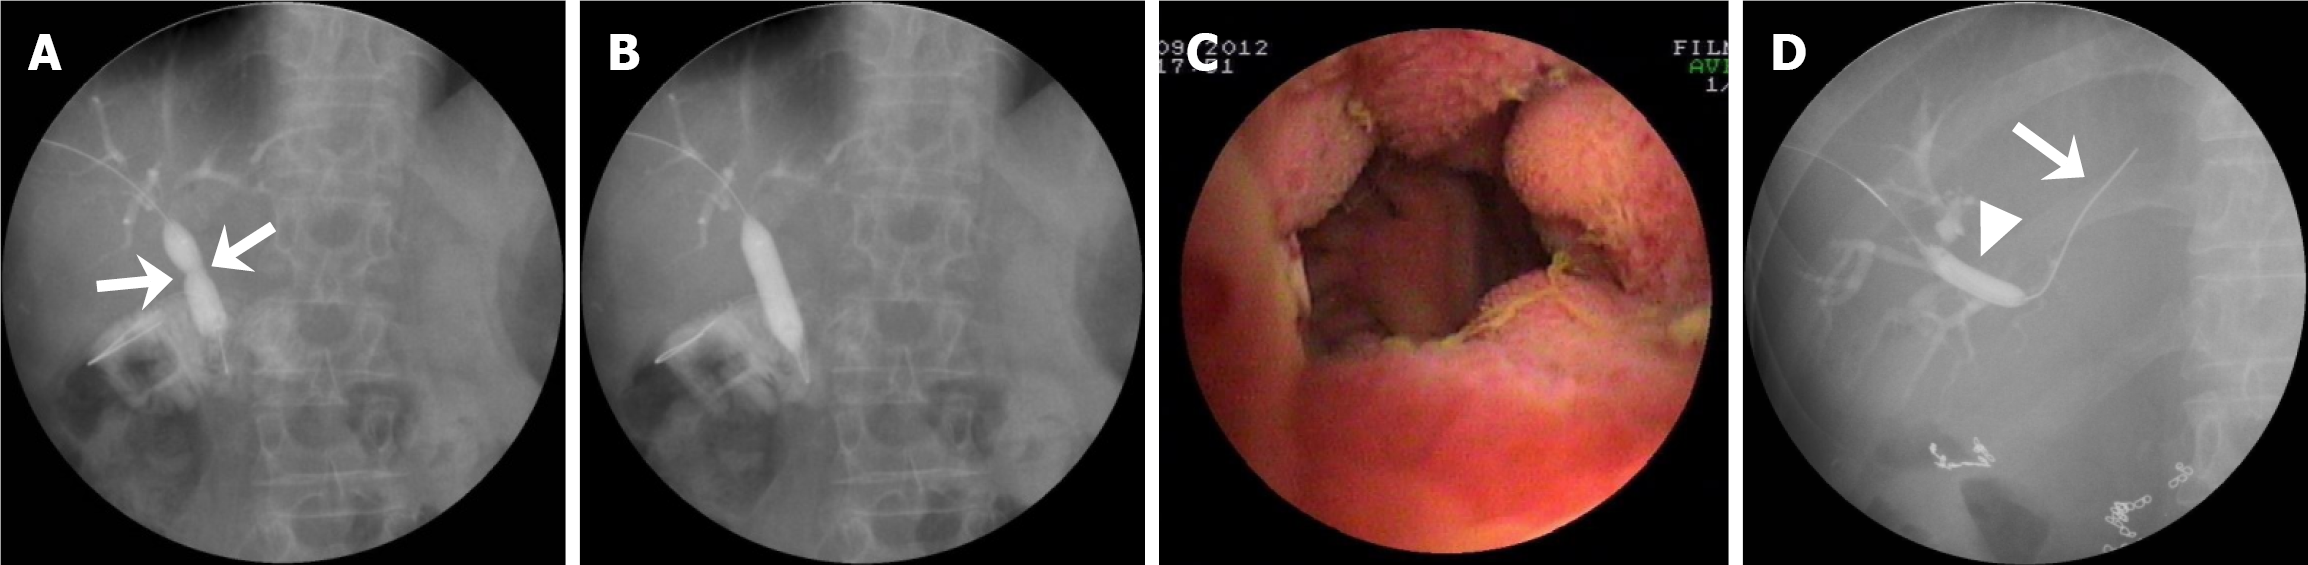

PTCS-assisted stricture dilation, anastomotic recanalization, and biliary stone therapy were performed in 31, 8, and 36 patients, respectively (Figure 1). Specifically, of the 40 patients, 31 patients (including 2 with mild, 11 with moderate, and 18 with severe anastomotic strictures) received BD (n = 27) (Figure 2A-C) or bougie dilation (n = 4). Nine patients did not receive stricture dilation due to complete anastomotic occlusion with failed anastomotic recanalization (n = 1) or mild strictures (n = 8). The eight patients with complex strictures achieved successful BD through PTCS-assisted guidewire passage beyond the stricture (Figure 2D). Among the 19 patients with a severe stricture, 11 patients received stricture dilation without pre-recanalization, and 8 patients received PTCS-assisted recanalization with a guidewire (n = 4, Figure 3A-C), microcatheter and microguidewire system (n = 2, Figure 3D-G), or a needle knife (n = 2, Figure 3H-O). The recanalization procedure was successful in seven (87.5%) of these patients who subsequently received stricture dilation by a balloon dilator (Supplementary Figure 1A and B) or a plastic bougie (Figure 3D-G). Of the 36 patients with biliary stones (9 and 27 with extrahepatic stones and intrahepatic stones, respectively), 20 and 16 patients received EHL/LL and stone removal with basket, respectively (Figure 4A-D).